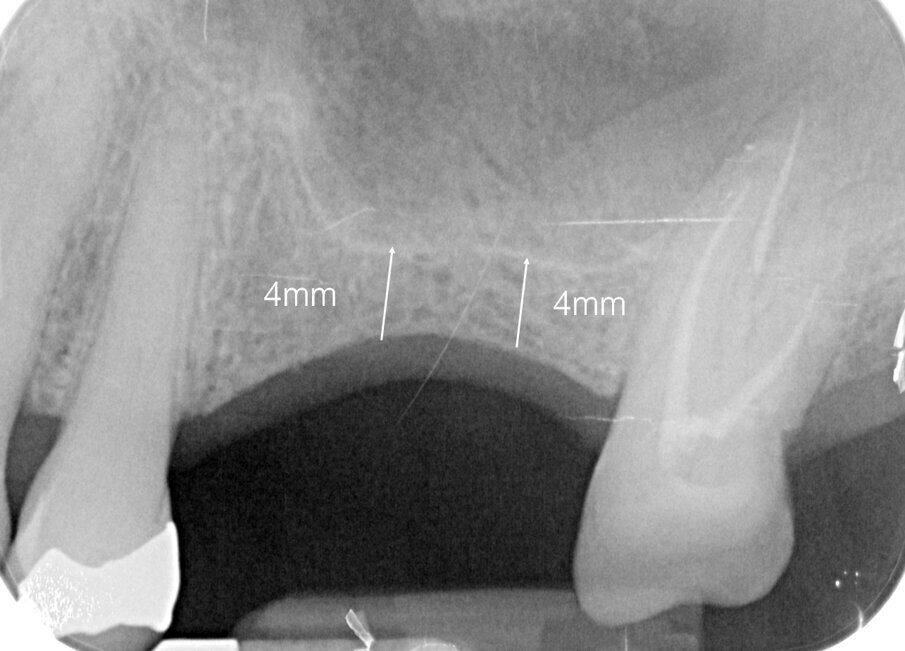

La sutura è stata rimossa 10 giorni dopo. A distanza di quattro mesi, gli impianti sono stati scoperti e si è proceduto a posizionare le viti di guarigione; dopo ulteriori tre settimane, constatato l’ottimo condizionamento dei tessuti molli, si è acquisita una ulteriore radiografia endorale (Fig. 7) e si è presa un’impronta per potere fabbricare la protesi provvisoria, che è stata consegnata dopo 10 giorni (Fig. 8). La protesi definitiva, in metallo-ceramica, è stata consegnata dopo ulteriori tre mesi, avendo cura anche di sostituire l’otturazione in amalgama che interessava l’elemento 2.4 con una in resina composita (Fig. 9). Il paziente è stato sottoposto ad una visita di controllo dopo 6 mesi. Sono pianificate ulteriori visite di controllo ogni 6 mesi, ciascuna comprendente una seduta di igiene orale completa e la usuale valutazione clinica e radiografica.

Fig. 7 - Condizionamento dei tessuti molli ed endorale di controllo.